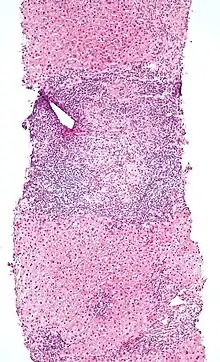

Low magnification micrograph of PBC. H&E stain.

On microscopic examination of liver biopsy specimens, PBC is characterized by chronic, non-suppurative inflammation, which surrounds and destroys interlobular and septal bile ducts. These histopathologic findings in primary biliary cholangitis include the following:[34]

- Inflammation of the bile ducts, characterized by intraepithelial lymphocytes, and

- Periductal epithelioid granulomata.

- Proliferation of bile ductules

- Fibrosis (scarring)

The Ludwig and Scheuer scoring systems have historically been used to stratify four (1–4) ‘stages’ of PBC, with stage 4 indicating the presence of cirrhosis. In the new system of Nakanuma, the stage of disease is based on fibrosis, bile duct loss and features of cholate-stasis, i.e. deposition of orcein-positive granules, whereas the grade of necroinflammatory activity is based on cholangitis and interface hepatitis. The accumulation of orcein-positive granules occurs evenly across the PBC liver, which means that staging using the Nakanuma system is more reliable regarding sampling variability.

Liver biopsy for the diagnosis and staging of PBC lost favour after the evidence of a patchy distribution of the duct lesions and fibrosis across the organ. The widespread availability of non-invasive measures of fibrosis means that liver biopsy for staging of PBC is somewhat obsolete. Liver biopsy does, however, remain useful in certain settings. The main indications are to confirm the diagnosis of PBC when PBC-specific antibodies are absent and confirm a diagnosis of PBC with AIH features (i.e. overlap PBC-AIH). Liver biopsy is also useful to assess the relative contribution of each liver injury when a comorbid liver disease is present, such as non-alcoholic steatohepatitis. In patients with inadequate response to UDCA, liver biopsy may provide the explanation and could undoubtedly inform risk stratification. For example, it may identify a previously unsuspected variant syndrome, steatohepatitis, or interface hepatitis of moderate or greater severity. It is also useful in AMA and ANA-specific antibody negative cholestatic patients to indicate an alternative process, e.g. sarcoidosis, small duct PSC, adult idiopathic ductopenia.